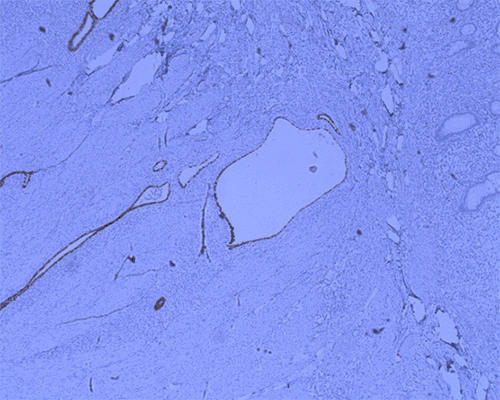

She underwent an EGD and colonoscopy, which was notable for a 30 mm polypoid appearing lesion coming from the appendiceal orifice (Figure 1) and an otherwise normal colon. Biopsies of the lesion showed fragments of colonic mucosa with hyperplastic change, fibrosis, crypt architecture distortion, and focal mild acute and chronic inflammation. A CT showed a tubular structure within the cecum measuring approximately 5 cm in length and 1 cm in width, concerning for an inverted appendix (Figure 2).

Figure 1. Colonoscopy Image of Inverted Appendix. Published with Permission

She underwent diagnostic laparoscopy. In the operating room, the appendix and the mesoappendix appeared to be partially intussuscepting into the cecum (Figure 3). It could not be reduced. There were no other abnormalities throughout her abdomen. A laparoscopic appendectomy and partial cecectomy were then performed (Figure 4). The specimen was taken en bloc without needing anastomosis (Figure 5). The frozen section in the operating room was negative for malignancy. Histopathologic evaluation of the specimen revealed an inverted appendix with endometriosis, surface erosion, serrated change, and reactive nuclear atypia. Sections demonstrated endometrial-type glands and stroma involving the appendiceal wall. Positive staining for ER, CK7, and PAX8 supports the diagnosis of an inverted appendix with endometriosis (Figure 6). It was negative for malignancy.

Figure 6. Immunostaining Profile, Demonstrating Endometriosis: A) CK7; B) ER, and C) PAX8. Published with Permission

A) Immunostaining Profile, Demonstrating Endometriosis: CK7

B) Immunostaining Profile, Demonstrating Endometriosis: ER

C)  Immunostaining Profile, Demonstrating Endometriosis:  PAX8